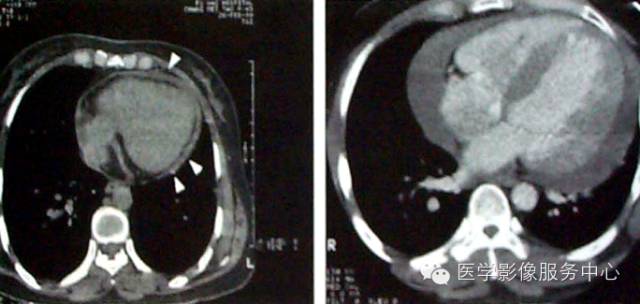

CT表现为:包腔增宽,心包腔内液体呈水样密度。CT值介于12HU~40HU之间,血性及渗出液CT值较漏出液及乳糜液CT值较低。少量积液仰卧位主要集中在左室背侧,中量积液对扩展至心脏腹侧,大量积液时可包裹所会心脏及大血管根部,下界可达BNJ水平,心包壁层、脏层间距明显增宽。

III度为大量积液,积液量>500ml,心包脏、壁层间距>25mm。

在MRI上,心包积液的信号强度依所选用脉冲序列和积液性质而不同。SE序列T1WI上多呈均匀低信,GRE序列呈高信号,如果心包积液内蛋白含量较高,T1WI可是不均匀高信号。血性积液则依血液成分的多少,呈中等或低信号。在T2WI上心包积液多为高信号。